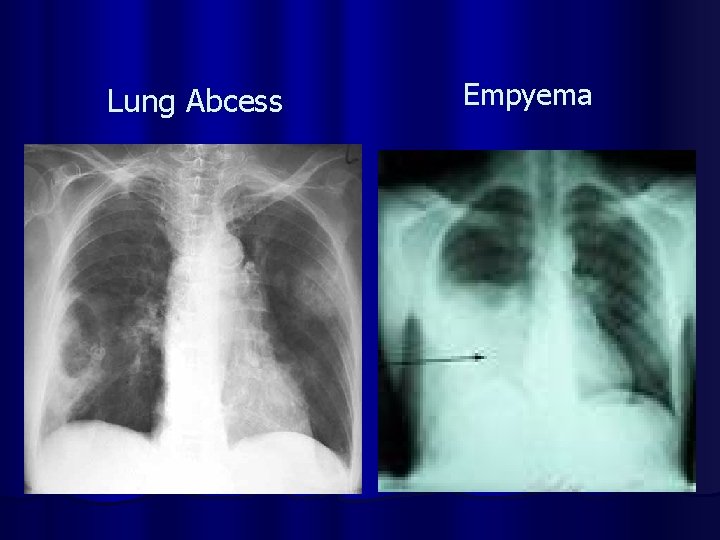

Lung Abcess Empyema

COMPLICATIONS OF PNEUMONIA l Parapneumonic effusion l Empyema l Sepsis l ARDS l Lung abcess l Focal Bronchiectasis